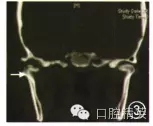

1.病例1:男性,72歲,因左側(cè)外耳道腫脹、流膿3個(gè)月并張口受限近1個(gè)月就診??谇豢茩z查:左側(cè)耳廓皮膚輕度腫脹變厚、暗紅色,外耳道皮膚腫脹明顯、觸痛,其前下壁有一3 mm直徑瘺口,顳下頜骨關(guān)節(jié)區(qū)腫脹、壓痛,有膿性分泌物溢出,張口中度受限,左后牙開(kāi)殆,顳下頜關(guān)節(jié)三維CT檢查示:左髁突局部有骨質(zhì)缺損,周圍軟組織腫脹模糊(圖1)。既往有糖尿病、高血壓、心臟病病史,空腹血糖12.3 mmol/L,血壓160/100mmHg(1 mmHg=0.133 kPa),C反應(yīng)蛋白偏高,膿液細(xì)菌培養(yǎng)為銅綠假單胞菌,心電圖示心肌缺血。

圖1病例1術(shù)前CT示死骨形成(箭頭)